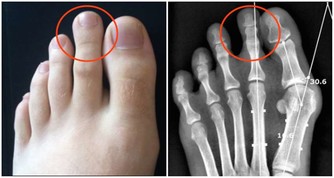

俗話說得好:「病來如山倒;病去如抽絲」...實際上,任何疾病的發生發展都有一個過程,在突發前都有一些身體上的先兆,只不過沒有引起我們足夠的重視罷了。隨著健康意識的增強,我們應該對人體發出的不良信號,給予足夠的重視,避免釀成大禍. 翻拍wikihow 一、起床後的四個信號 人的一天在不同階段身體的不良感受,就是在向您的健康發出警示信號。 1、清晨醒來如果頭暈、頭昏,可能是出現了頸椎骨質增生或血黏度過高等疾病; 2、如果在起床活動20分鐘後浮腫還不徹底消失,提示可能有腎病或心臟病; 3、晨起噁心嘔吐,除去懷孕的原因,如每天早上都如此,很可能是慢性胃炎或肝膽有病; 4、晨起小便,如果尿液棕色,提示肝臟可能出現問題。 二、清晨對鏡觀察臉色 洗臉時對著鏡子觀察,看看自己的臉色有沒有什麼異常: 1、如果發現自己臉色潮紅,可能與心臟病或高血壓有關; 2、如臉色帶黃,還伴以身體疲倦,很可能是黃疸型肝炎; 3、如發現眼睛顏色改變,充血、渾濁、色黃,應馬上去醫院看醫生; 4、如眼瞼蒼白,提示可能患了缺鐵性貧血; 5、如眼角膜出現一圈模糊的灰環,說明心臟可能有問題,如果是30—50歲的男性應馬上到醫院就診。 三、刷牙留意牙齒口氣 1、刷牙時如果牙齦出血,很可能是牙周病,因為如果牙齒健康是不會出血的。牙齒出血也可能與肝病有關。這種現象在慢性肝病患者中很普遍,還會伴有鼻子流血、月經過多。主要原因是肝細胞損傷後,肝臟產生凝血因子的功能下降,繼而凝血機制發生障礙。一般牙出血的肝炎病人可以服用維生素C、維生素K及其他止血藥來緩解病情。 2、如果出現口臭、口氣重,則可能是牙周病引起,同時,胃病、肝病、糖尿病等全身性疾病或缺乏微量元素鋅和維生素B都可能導致口臭。比如,胃幽門螺桿菌感染可引起持續性口臭,還常伴有不同程度的飢餓感和胃痛。一旦吃飽喝足,口臭會隨之減輕,而隨著幽門螺桿菌的根治,口臭也會自動消失。 3、口中有氨味要格外注意腎臟的健康。當腎功能衰竭時,由於不能正常代謝,體內肌酐、尿素氮含量增高,口中就有一股特殊的氨氣味。 四、飲食上的大病先兆 1、如果總感到口渴,要去查查血糖和糖耐量,看有沒有可能是糖尿病; 2、如果在清晨4—5點鐘醒來有強烈的心慌飢餓感,並且伴有疲乏無力,直到吃早餐後不舒適的感覺才逐漸消失,提示可能是糖尿病傾向; 3、如果吃油膩食物後上腹部疼痛,並放射到右肩背部,很可能是患有肝膽疾病; 4、如果食慾亢進,體重卻減輕,可能患了甲狀腺功能亢進症; 5、如果沒有食慾,見到油膩就噁心,易疲勞,可能是患了肝炎; 6、如果出現食不知味,並伴心悸、多夢、失眠等。這就意味著心臟功能受到了損害,是操勞過度所致。當口中乾澀,舌苔厚重,嘗不出食物的滋味時,尤其要警惕,防止心臟發生病變; 7、如果飯後總是出現反酸、腹脹或腹痛等症,提示積食了,要多吃新鮮蔬菜,三餐要注意清淡,以易於消化。 五、手部的警示信號 1、觀察自己的雙手,如果發現指尖比指節更粗大,可能是患有較嚴重的肺部疾病; 2、如果指甲生長緩慢,沒有光澤並且變黃變厚,提示淋巴系統出了毛病; 3、如果手背靜脈突出,並且隨著年齡增加越加明顯,也提示有心臟病的可能; 4、如果手掌泛紅,可能是肝臟出現問題及內分泌失調; 5、如果過度興奮或緊張時手掌常潮濕出汗,可能有甲狀腺的異常; 6、手發抖可能是甲亢,也可能是帕金森病。 六、眼睛的警示信號 1、眼睛發花,眼角乾澀,看不清東西。這是肝功能衰弱的先兆。如果按一按肝臟四周,就會有發脹的感覺,這時除了及時就醫外,還要注意用眼衛生,不要讓眼睛太疲勞; 2、如果經常眼睛疼痛,除了用眼疲勞外,老年人出現這種情況要提防青光眼。